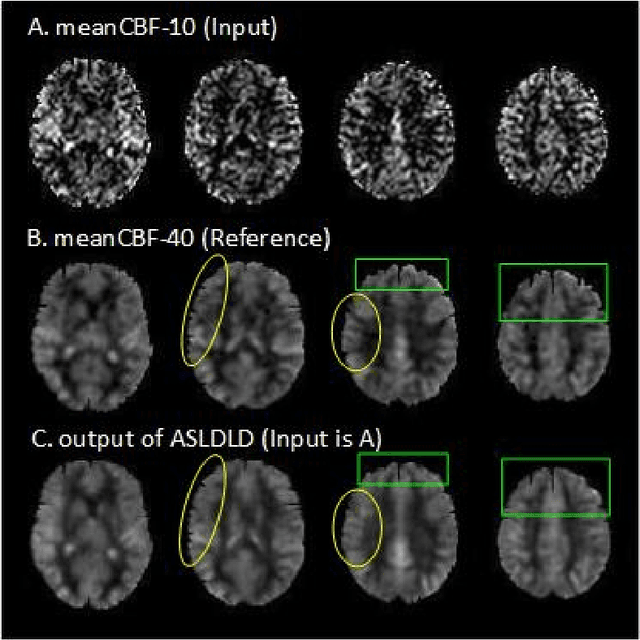

Abstract:Arterial spin labeling (ASL) perfusion MRI provides a non-invasive way to quantify cerebral blood flow (CBF) but it still suffers from a low signal-to-noise-ratio (SNR). Using deep machine learning (DL), several groups have shown encouraging denoising results. Interestingly, the improvement was obtained when the deep neural network was trained using noise-contaminated surrogate reference because of the lack of golden standard high quality ASL CBF images. More strikingly, the output of these DL ASL networks (ASLDN) showed even higher SNR than the surrogate reference. This phenomenon indicates a learning-from-noise capability of deep networks for ASL CBF image denoising, which can be further enhanced by network optimization. In this study, we proposed a new ASLDN to test whether similar or even better ASL CBF image quality can be achieved in the case of highly noisy training reference. Different experiments were performed to validate the learning-from-noise hypothesis. The results showed that the learning-from-noise strategy produced better output quality than ASLDN trained with relatively high SNR reference.

Abstract:Arterial spin labeling perfusion MRI is a noninvasive technique for measuring quantitative cerebral blood flow (CBF), but the measurement is subject to a low signal-to-noise-ratio(SNR). Various post-processing methods have been proposed to denoise ASL MRI but only provide moderate improvement. Deep learning (DL) is an emerging technique that can learn the most representative signal from data without prior modeling which can be highly complex and analytically indescribable. The purpose of this study was to assess whether the record breaking performance of DL can be translated into ASL MRI denoising. We used convolutional neural network (CNN) to build the DL ASL denosing model (DL-ASL) to inherently consider the inter-voxel correlations. To better guide DL-ASL training, we incorporated prior knowledge about ASL MRI: the structural similarity between ASL CBF map and grey matter probability map. A relatively large sample data were used to train the model which was subsequently applied to a new set of data for testing. Experimental results showed that DL-ASL achieved state-of-the-art denoising performance for ASL MRI as compared to current routine methods in terms of higher SNR, keeping CBF quantification quality while shorten the acquisition time by 75%, and automatic partial volume correction.